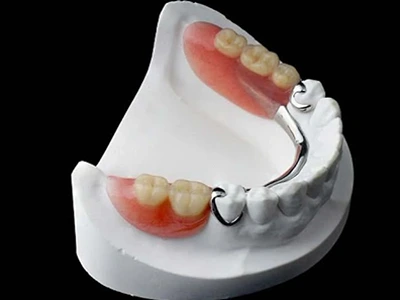

Dr Nitesh Rai, specializes in replacement of teeth with complete dentures, removable partial dentures, fixed partial dentures and Implants.